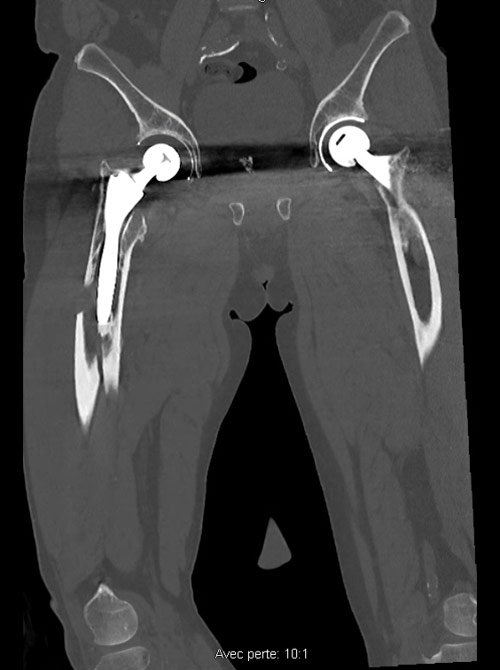

A 71-year-old male, who underwent a right Total Hip Arthroplasty (THA) 12 years ago and a left THA 5 years ago for hip osteoarthritis, recently experienced a fall while walking. Which classification system is appropriate for categorizing the fracture observed in the imagery, and what specific grade? Considering the patient's age, history of bilateral THA, and the nature of the fracture, how would you approach the management of this condition?

Imagery

Peri prostetic femoral fracture - Imagery

Which classification allows us to categorize this fracture and what is its grade?

• ✔️Vancouver classification grade B2